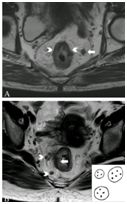

前腹膜返折(APR)是区分腹膜内和腹膜外直肠的重要标志,直肠癌伴腹膜返折受累为T4,增加肿瘤侵入腹腔风险。轴位T2加权像膜返折为薄层中线包绕筋膜返折,称为V型或海鸥征,女性子宫宫颈角和男性精囊腺尖端也是可靠标志(图7)。

图7  腹膜返折。A. 轴位T2加权像海鸥征(长箭头);B. 矢状位T2加权像腹膜返折的线状低密度信号位于子宫宫颈角(长箭头)。

MRI不能显示所有APR,如<1mm低密度线影,此外大的外生性直肠癌、盆腔腹膜脂肪缺乏和术后时APR均较难检测到,如下策略有助于发现APR:获取真正的中线矢状和矢状旁图像;解痉药减少运动伪象改善图像质量;半空膀胱使子宫和前腹壁距离更近,更易鉴别APR;盆底积液也增加发现APR机会。